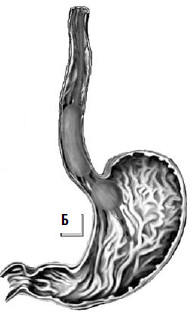

В патогенезе асцитического синдрома принимают участие многочисленные факторы, которые могут быть условно отнесены к местным (регионарным) и общим (системным). К регионарным факторам относят: синусоидальную гипертензию, повышенное лимфообразование, лимфатическую гипертензию. К системным факторам относят: гипоальбуминемию, активацию ренин‑ангиотензин‑альдостероновой системы, задержку натрия и воды. Синусоидальная гипертензия возникает при внутрипеченочной портальной гипертензии, вызывает повышенную транссудацию плазмы, богатой белком, в пресинусоидальное пространство Диссе, что приводит к значительному лимфообразованию в печени и увеличению числа отводящих внутрипеченочных лимфатических сосудов. Значительное увеличение истечения лимфы из грудного протока во внутреннюю яремную вену приводит к функциональной недостаточности терминального отдела грудного протока с развитием повышенного давления в лимфатической системе. Г ипоальбуминемия, возникающая вследствие нарушения белковосинтетической функции печени, приводит к снижению онкотического давления и повышению объема интерстициальной жидкости, что вызывает пропотевание жидкости в брюшную полость. Развитие варикозного расширения вен пищевода (равно как вен прямой кишки и передней брюшной стенки) является следствием портальной гипертензии и перестройки циркуляции венозной крови в спланхническом регионе. При этом часть воротной крови начинает оттекать по предсуществующим и малозначимым в норме внепеченочным портокавальным анастомозам (пищеводным, ректальным, передней брюшной стенки) (рис. 81).

Рис. 81. Портокавальный переток в норме (А); при циррозе печени (Б). 1) печень; 2) пищеводные портокавальные анастомозы; 3) ректальные портокавальные анастомозы; 4) портокавальные анастомозы передней брюшной стенки.

Эти пути варикозно расширяются, принимая на себя значительную часть крови из воротной системы, компенсируя нарушение венозного кровотока в печени. Но даже при значительном расширении не наступает адекватной компенсации. Кроме того, печень, не получая достаточно крови, не выполняет свои синтетические и детоксикационные функции. Развивается гипопротеинемия, гипокоагуляция, гипоферментемия, что ограничивает обменные процессы в тканях. Продукты метаболизма и токсины, всосавшиеся в кишечнике минуя печень, где должны быть обезврежены, в неизмененном виде поступают в системный кровоток, вызывая аммиачную интоксикацию, энцефалопатию и кому. Таковы механизмы развития портальной гипертензии и ее осложнений – асцитического синдрома, варикозного расширения вен пищевода и печеночной недостаточности.